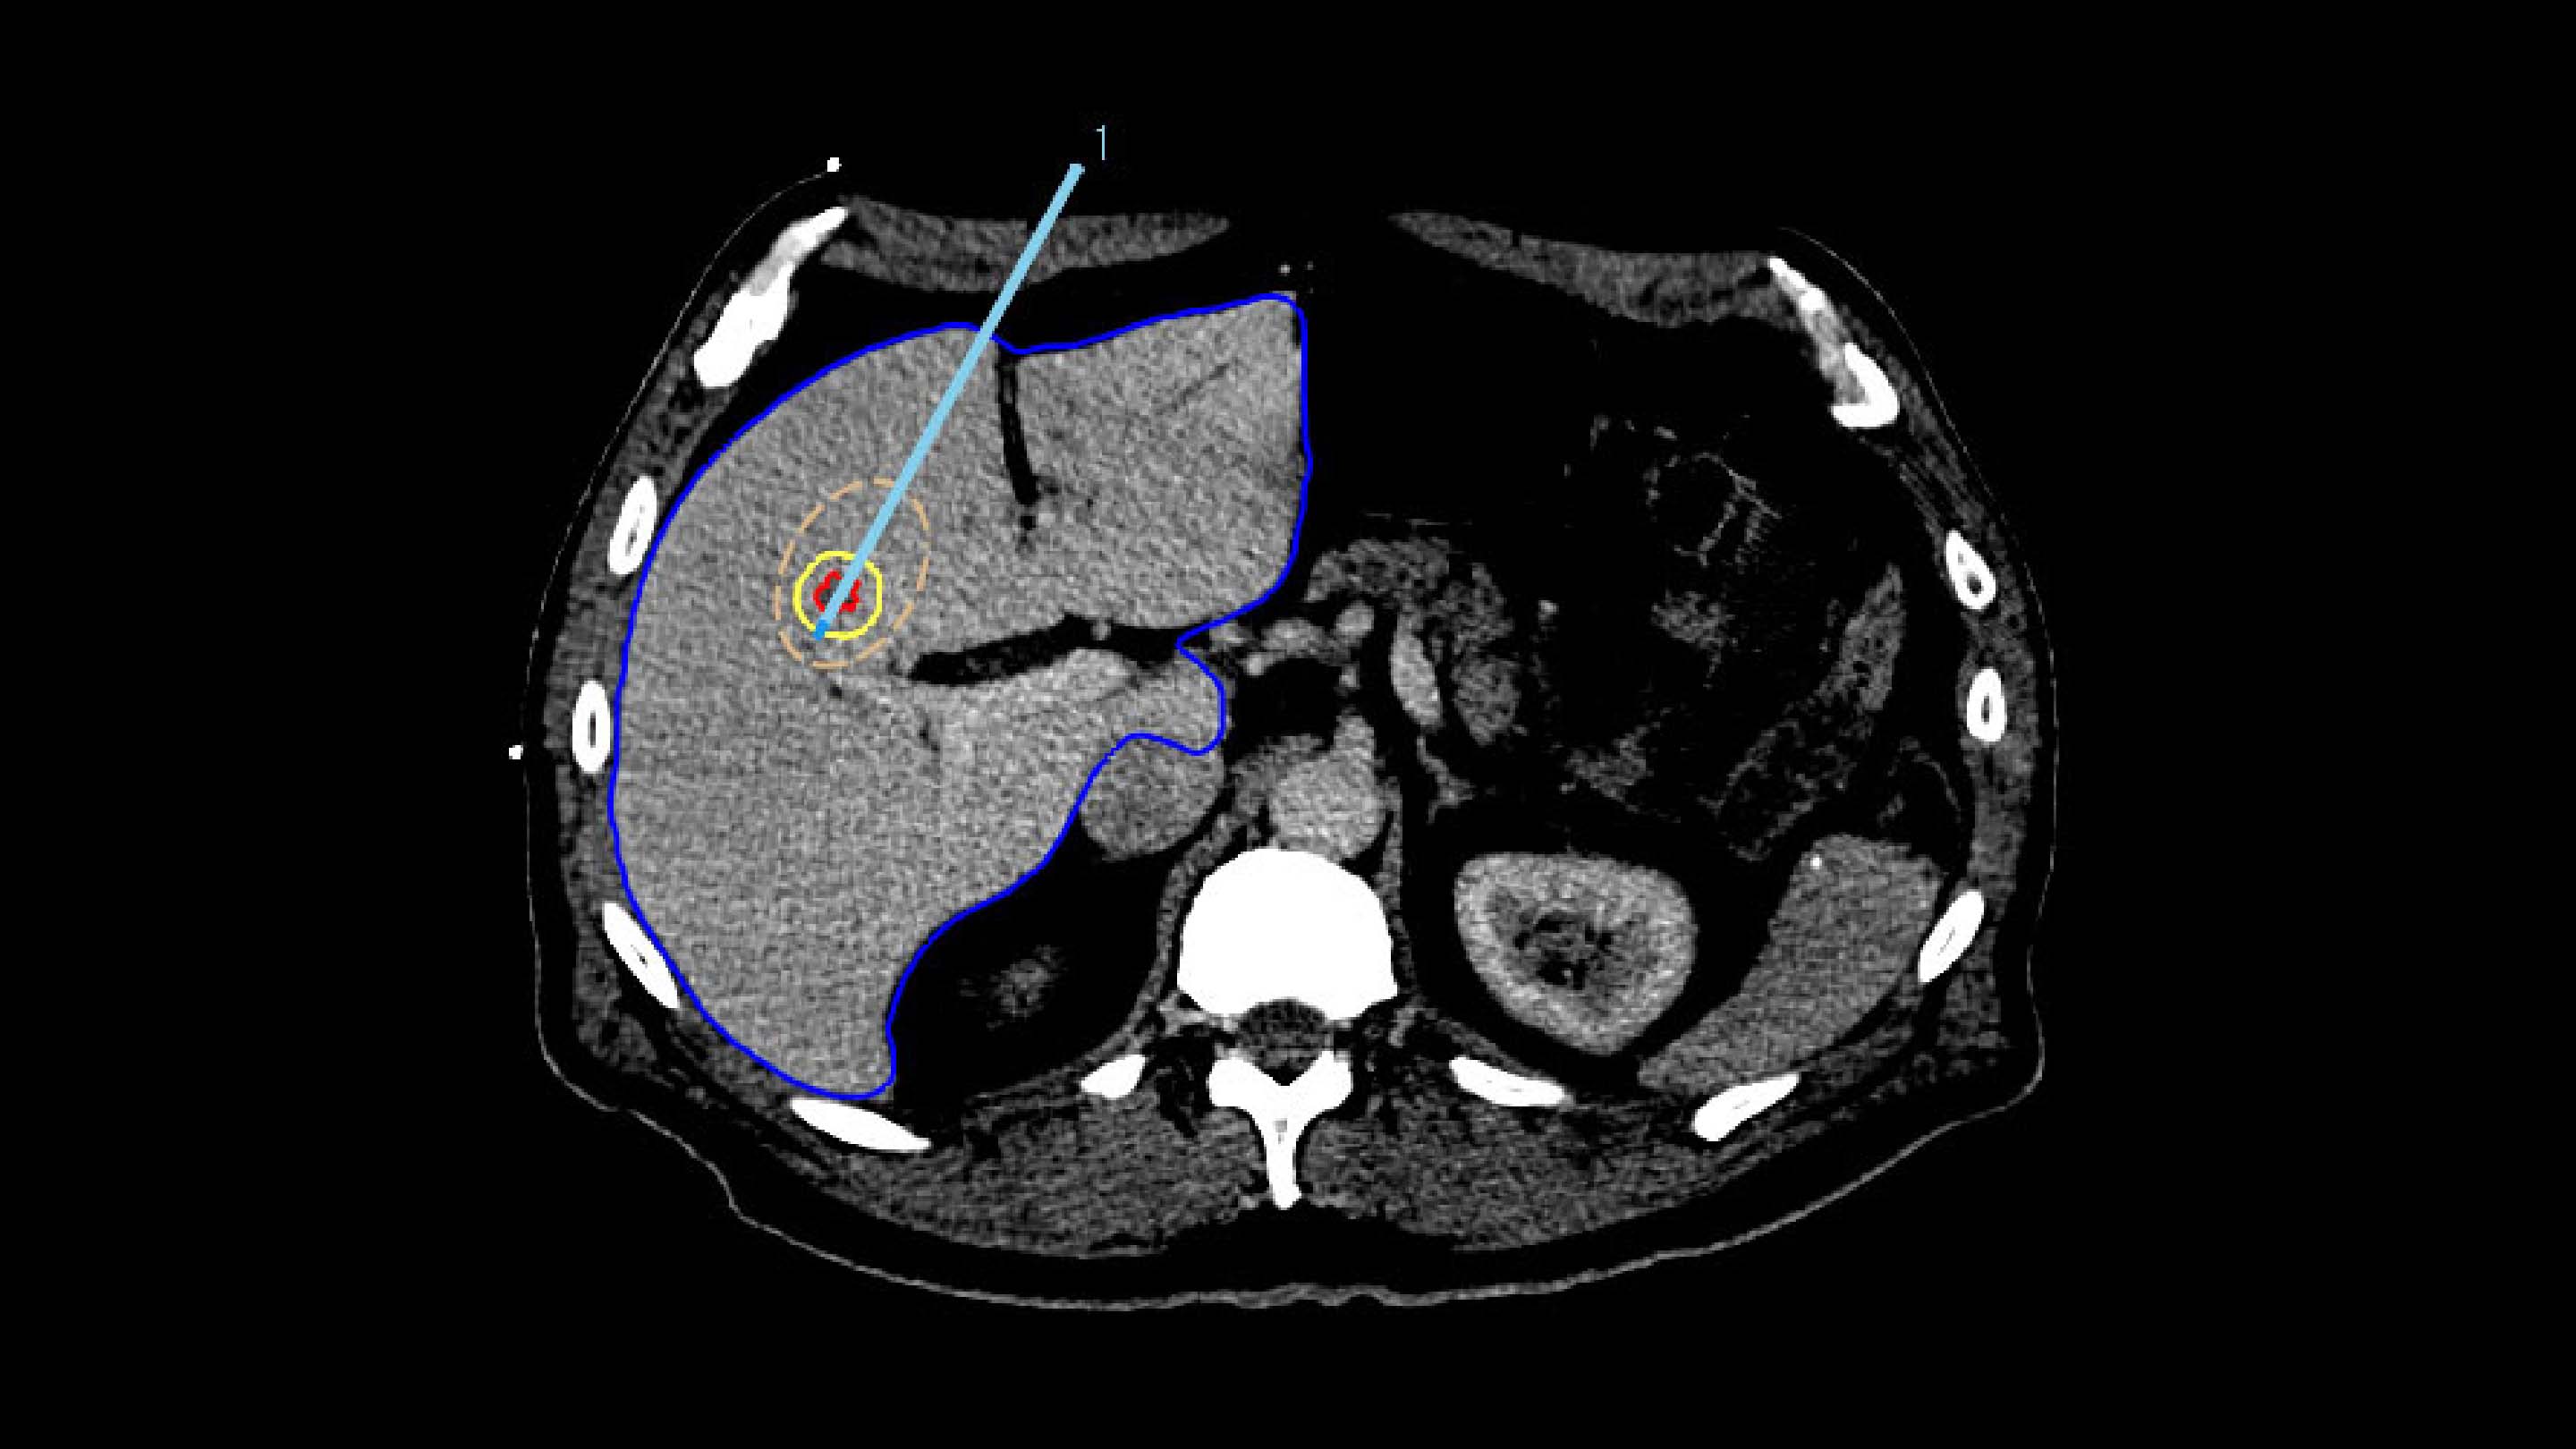

3. VERIFICATION

For treatment verification, both the minimal ablative margin calculation and visual inspection based on deformable mapped tumors are provided in the Liver Ablation module.

In Paulucci et al., it was shown that using biomechanical deformable registration, the local disease progression risk decreased to less than 1% with an intraprocedurally confirmed minimum ablative margin greater than 4.6 mm.